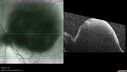

Last additions - Ruptured Macroaneurysm and BRAO 81 year old female The vision in the left eye declined a few days ago. Her coumadin level was high recently. She had stopped the coumadin for eye surgery. Then when she went back on the coumadin her levels were high (3.1).

Ruptured Retinal Arterial Macroaneurysm - Submacular hemorrhage and BRAO95 views81 year old female with vision loss for a few days. Coumadin was high with INR at 3.1 VA 6/200Dec 21, 2024